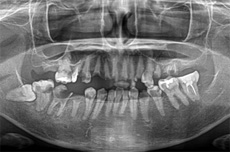

当院で治療された方の症例集をご覧ください!

オールオン4の治療例:1

治療前

治療後

オールオン4の治療例:2

その他 ボロボロ虫歯の症例